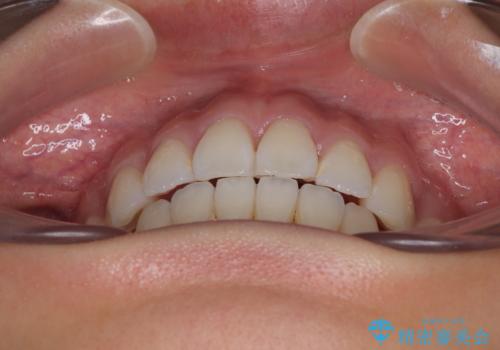

- 前歯が突出して、眠るときに口が開いてしまうことを気にして来院された患者様です。

横から見た際の口元の飛び出した印象も改善したいとのことで、上下左右の第一小臼歯4本を抜歯し、ワイヤー装置にて抜歯矯正を行うこととしました。

舌の突出癖改善のためのトレーニングをしっかりと実践してくださり、2年強の治療期間でしっかりと仕上げることができました。